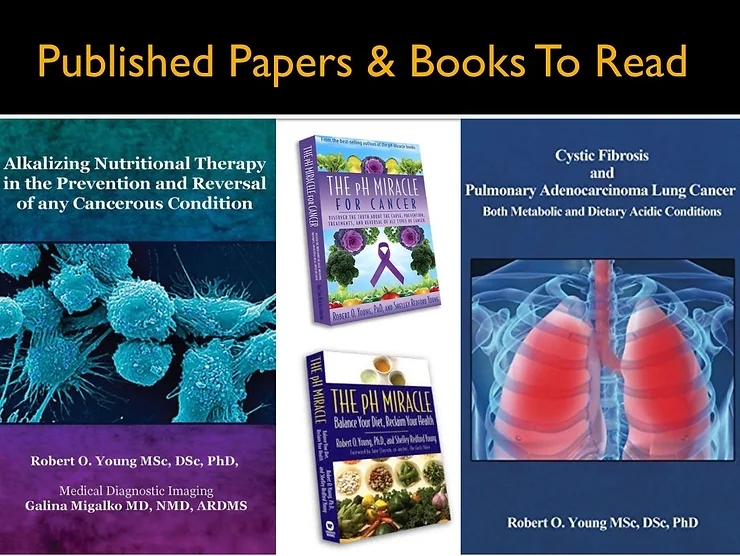

2. The pH Miracle revised and updated, The pH Miracle for Diabetes, The pH Miracle for Weight Loss, The pH Miracle for Cancer, Alkalizing Nutritional Therapy in the Prevention and Treatment of Any Cancerous Condition, Metabolic and Dietary Acids Are the Fuel That Lights the Fuse That Ignites Inflammation That Leads to Cancer and The Cause and Cure for Atherosclerosis and Coronary Artery Disease, by Robert O. Young CPT, MSc, DSc, PhD, Naturopathic Practitioner